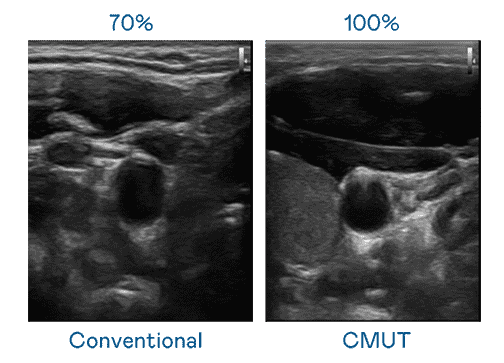

CMUT 技术是一种用电容式微机电元件来产生超音波讯号的技术。。。与传统 PZT 压电式技术相比,,CMUT 频宽增加 30%,,,,更宽频的超音波讯号让影像解析度大幅提升,,是实现高影像品质医疗超音波扫描、、、、促进精准医疗发展的关键技术。。

大频宽带来超清晰影像

超音波影像的解析度高低,,首先取决于探头能发出的讯号频宽。。。尊龙集团 CMUT 可提供高清晰的超音波讯号,,,提供高频宽、、高灵敏度、、影像纹理细节更高的超音波影像,,协助医护人员缩短影像判读时间及利用精准的医疗影像进行诊断。。。